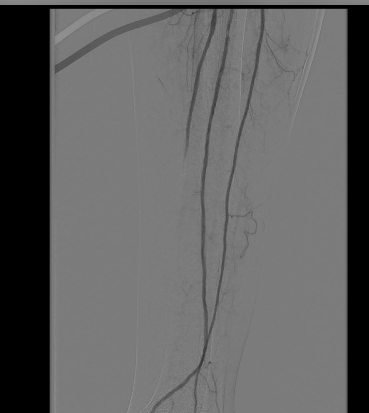

تفاصيل الإنجاز، أوضح استشاري الأشعة التداخلية وقائد الفريق الطبي، الدكتور أحمد الثويمر، أن المريض كان يعاني من حالة متقدمة من انسداد وتكلسات حادة في شرايين الساق اليسرى، مما أدى إلى نقص حاد في التروية الدموية وتفاقم التقرحات بشكل خطير.

أشار إلى أن التدخل النوعي باستخدام تقنية ”بالون الموجات التصادمية“ أتاح للفريق الطبي تفتيت التكلسات الصلبة داخل الشرايين بدقة وفعالية، ونجح في استعادة تدفق الدم بشكل طبيعي إلى الطرف، مما يعزز بشكل كبير فرص التئام الجروح وتجنب خيار البتر.